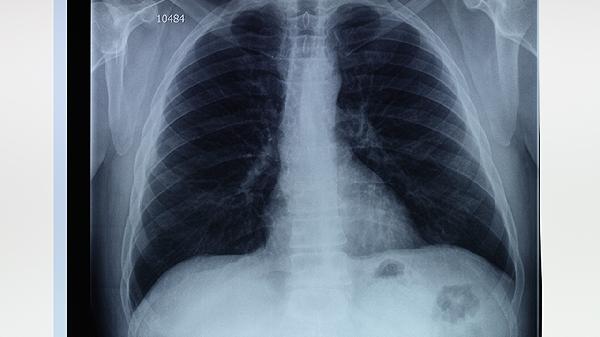

肺气肿和小肺大泡的严重程度取决于病变的范围和患者的身体状况。肺气肿和小肺大泡的严重性主要与病变范围、肺功能受损程度、并发症风险、症状表现及生活质量影响等因素有关。

肺气肿和小肺大泡的严重性与病变范围密切相关。病变范围越大,肺组织受损越严重,肺功能下降越明显。局限性病变可能对整体肺功能影响较小,而弥漫性病变则可能导致严重的呼吸功能障碍。

肺气肿和小肺大泡会导致肺功能下降,表现为肺活量减少、残气量增加、气道阻力增大等。肺功能受损程度越严重,患者的呼吸困难和缺氧症状越明显,严重时可能导致呼吸衰竭。